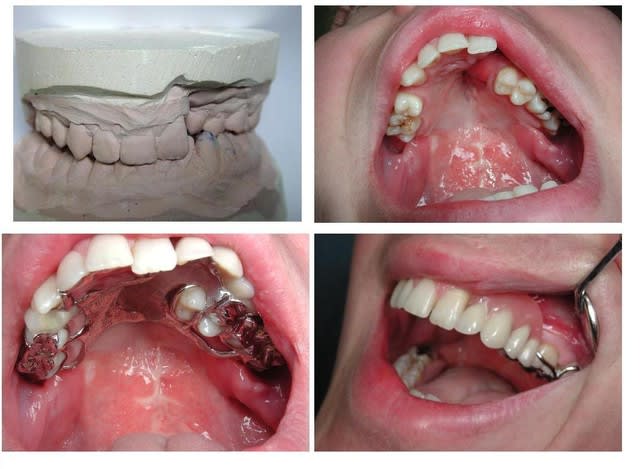

Patiente 50 ans

Syndrome de Down,

Pro-alvéolie maxilaire

Béance inter incisive

Agénésie incisives inf par hyper solicitation

Photos de primaires :

Enregistrement aléatoire d’après érosions visibles

Cadran 3 et 4 désiquilibre par manque d’occlusion

33 précaire à court terme en l’état

Photos de la secondaire inf :

Enregistrement primaire

Confection base résine, prenant appui sur toute partie dentaire supposée non interférente pour enregistrement, prévu s’tents et/ou alu wax